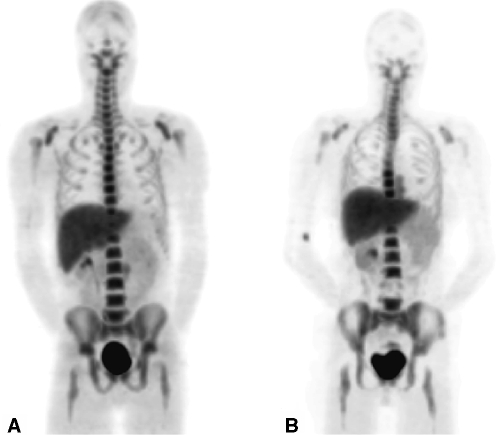

Fig. 1.

Different patterns of haematopoietic bone marrow imaging. a Normal pattern of haematopoietic bone marrow activity in the central skeleton and skull. b Expansion of haematopoietic bone marrow activity more distally in the extremities. c Reduced haematopoietic bone marrow activity in the central compartment of the skeleton and skull, as seen in AA. d MF with extramedullary erythropoiesis in the spleen and liver and reduced haematopoietic bone marrow activity in the central compartment of the skeleton and skull

Patients with MF show an extension of 111In-Cl3 uptake beyond the central skeleton towards the knees and sometimes ankles and elbows, together with uptake in the spleen. The clinical severity of the disease may be predicted by uptake of indium, particularly the disappearance of a physiologically active bone marrow (Fig. 1) [28]. 111In-Cl3 scintigraphy of the bone marrow has been reported in patients with AA before therapeutic intervention. In almost all patients a marked reduction in the uptake was seen. Failure of 111In-Cl3 uptake correlated with a poor prognosis in patients with AA [29]. Another study was performed in patients with AA in remission for more than 2 years. Bone marrow scintigrams using 111In-Cl3 showed patchy haematopoiesis which appeared to characterize the residual marrow damage in AA remission [30].